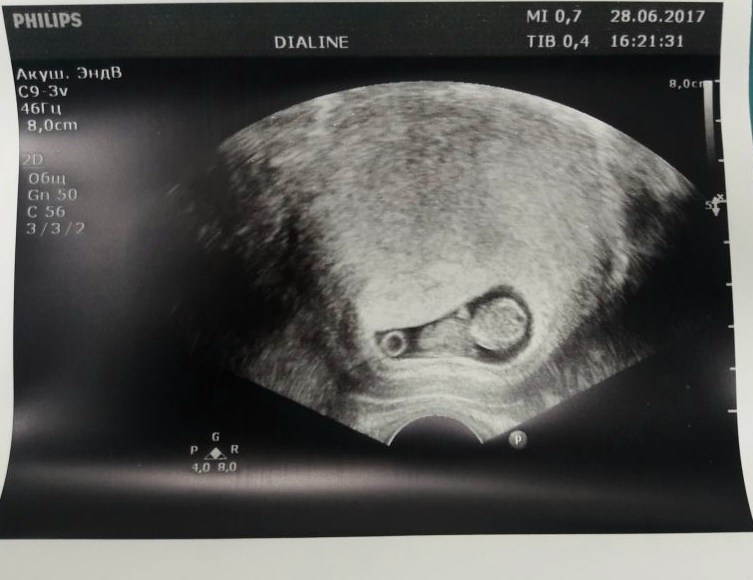

Наше первое УЗИ

Были на УЗИ 27.06.2017. Все у на схорошо, ростем! Папа был просто в вострге когда увидил нашего малютку😍😍😁 Оставлю тут фоточку на память!😇😇